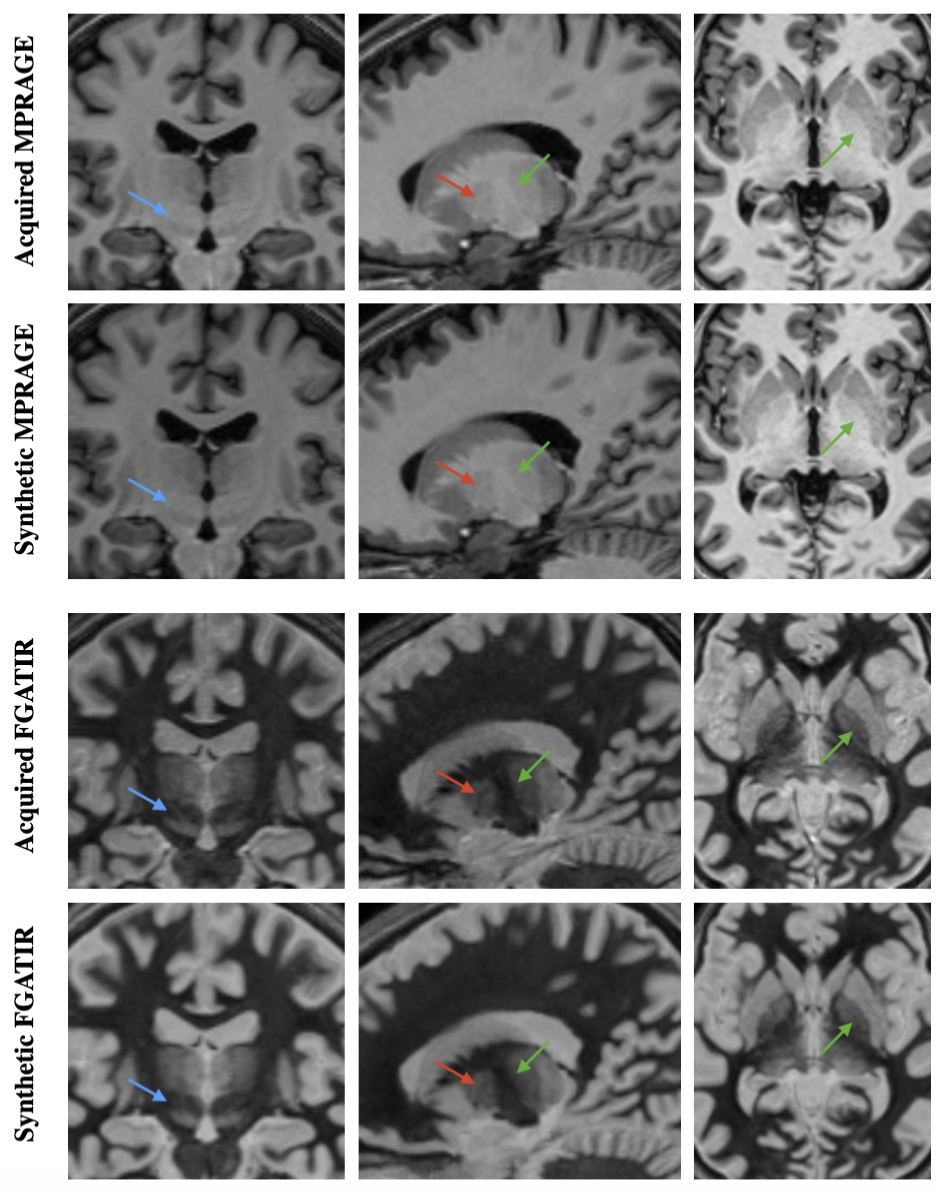

Figure 8 shows examples of multi-TI images computed from the T1T1 and ρ\rho maps corresponding to the ground truth and the three SyMTIC models. Figure 9 provides a visual comparison of an acquired and synthetic MPRAGE and FGATIR images in the axial, sagittal, and coronal planes. We highlight DBS targets in these images, demonstrating that these structures are clearly visible in both the acquired and synthetic FGATIR images. This qualitative comparison supports the potential of our model to enhance DBS planning through synthetic FGATIR image generation.

Refer to caption

Figure 9: Acquired MPRAGE, synthetic MPRAGE, acquired FGATIR, and synthetic FGATIR images (top to bottom). Arrows point to DBS targets that are less visible in MPRAGE images: blue for subthalamic nuclei, red for thalamic nuclei, and green for the internal lamina.